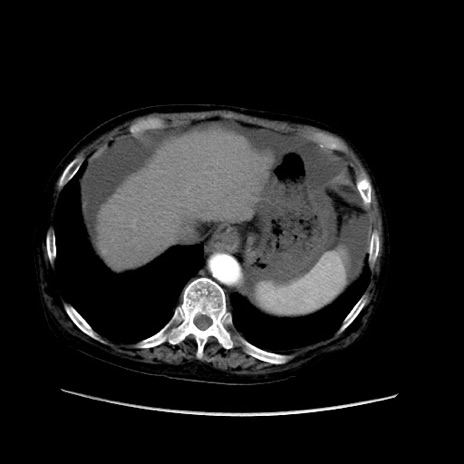

冠状断像

【症例】80歳代 女性

【主訴】腹部膨満感

【現病歴】他院にて肝硬変にてフォロー中。1週間前から便秘、腹部膨満感、臍部腫瘤あり受診となる。

【既往歴】肝硬変

【身体所見】腹部膨隆あり、皮膚変化なし、疼痛なし。

【データ】WBC 4600、CRP 0.25